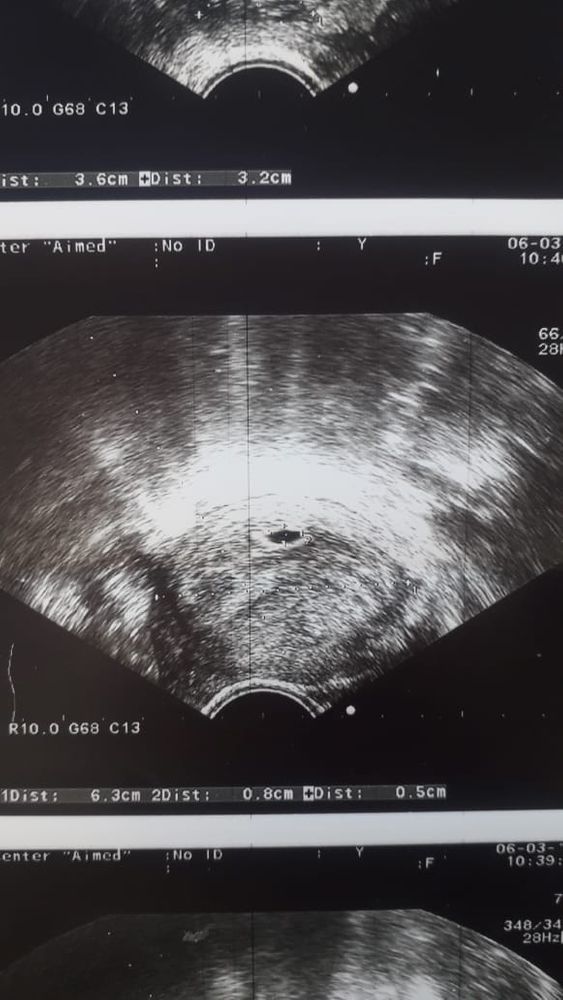

24 дпп узи

Ну вот моё второе узи. Пя немного подрос. И заметен жм. Эмбрион и сердцебиение ре сказала через две недели сделать узи.